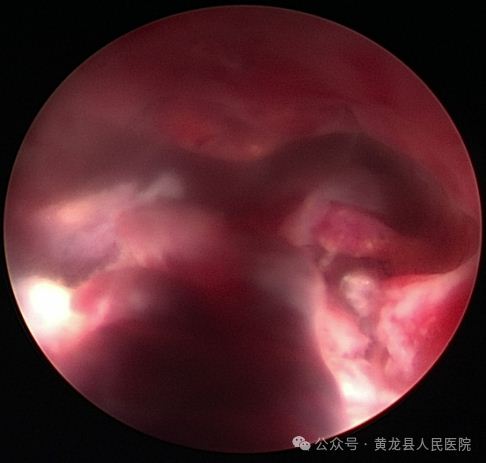

患者赵某,58岁,绝经后B超提示子宫内膜增厚8天。患者合并高血压,高血脂、盆腔炎,入院后给予降压、调脂、抗感染治疗后行宫腔镜检查术,术中见宫腔中上部可见一纤维状粘连,宫底及双侧输卵管开口不可见,宫腔下段前后壁分别可见一枚赘生物,大小约1×0.2cm、0.5×0.2cm,实施宫腔镜宫腔粘连分离术及宫腔镜子宫内膜息肉切除术,术后病检:子宫内膜息肉。

术前宫腔术后宫腔